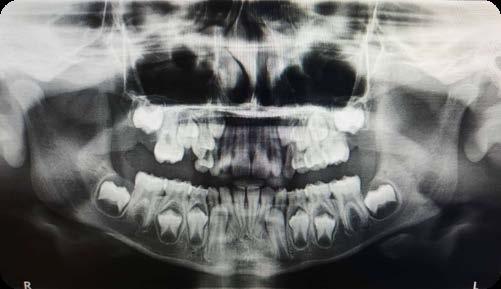

a. Observar radiográficamente las características anatómicas y dimensionales de los caninos superiores e inferiores respecto a dientes adyacentes (Figura 11).

b. Identificar radiográficamente la posición en que se encuentra el canino, respecto a los dientes adyacentes (Figura 12).

c. Determinar que angulación y posición existe entre el eje longitudinal

del canino respecto al plano oclusal, donde “V” es vertical, “M” es mesioangular, “H” es mesiohorizontal, “MI” vertical invertido, “D” distohorizontal (Figura 13).

A partir de los 8 años, se puede observar radiográficamente el inicio de la reabsorción del canino deciduo (Figura 17).

El seguimiento del trayecto canino con un estudio radiográfico postero anterior, lateral de cráneo y ortopantomográfico, a partir de la edad señalada anteriormente, también es una herramienta efectiva que permite obtener un diagnóstico inicial, donde podrá observarse si se ha iniciado la reabsorción radicular del canino deciduo e identificar qué

dirección o trayecto está tomando el canino permanente (Figura 18).

Power y Short afirman en su análisis, que si el ángulo resultante formado entre la línea vertical determinada por la espina nasal anterior y el eje longitudinal del canino sea mayor a 31°, el éxito del acomodo del canino en el arco dental es reservado (Camarena-Fonseca et al. ,2017) (Figura 19).

Ubicación del canino

Un método sencillo para obtener el diagnóstico de inclusión canina en proceso o declarada, cuando no se realizó un seguimiento desde una edad temprana, será utilizando como herramienta de diagnóstico inicial, una ortopantomografia, donde al trazar puntos, planos y líneas de referencia en estructuras dentocraneales y en el eje longitudinal del canino propiamente, podremos ubicar tridimensionalmente el sitio de inclusión en proceso de formación radicular (estadio del 6 al 9), o definitivo, cuando el ápice se ha cerrado (estadio 10 de Nolla) y el diente no erupcionó8 (Figura 20).

Así lo mencionan (Ericson y Kurol) (Etal Eur J Orthod. 1988; 10:283–95)4, en el que proponen una clasificación, utilizando como herramienta una ortopantomografía y la angulación del canino, usando planos, líneas de referencia y la determinación de sectores, ubicando a estos de la siguiente manera:

El sector IV incluye todas las áreas mesiales al sector III (Figura 21).

Por otro lado, como complemento a lo anterior, trazando una línea sobre el eje longitudinal del canino, la cual, hará referencia y marcará la angulación de su posición respecto a los planos siguientes:

1. Al plano oclusal, utilizando los primeros molares como referencia.

2. Plano de la línea media, perpendicular al oclusal entre los incisivos centrales superiores.

Paso seguido, habiendo analizado los resultados de las mediciones y angulaciones obtenidas, podremos referir lo siguiente:

1. Si la inclinación resultante de la posición canina es de 25° de inclinación de su eje longitudinal respecto a la línea media, será

considerada la norma ideal dentro de los límites naturales del intercambio dental, donde el canino lleva una dirección de erupción aceptable y de bajo riesgo.

2. Si la angulación aumenta, el riesgo de impactación del canino sobre el diente lateral, incrementará el riesgo de reabsorción radicular del diente lateral en un 50%, así como una franca inclusión (Figura 22).